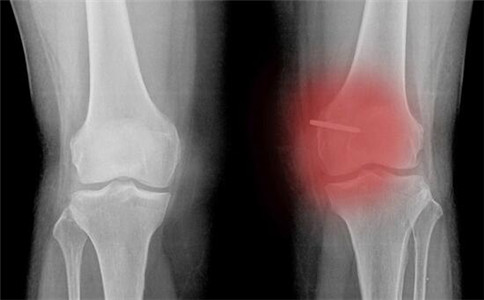

骨性關(guān)節(jié)炎

骨關(guān)節(jié)炎的特征:從軟骨退化開始的關(guān)節(jié)病變。統(tǒng)計分析顯示,大于50歲的人群當(dāng)中,有80%的人患有關(guān)節(jié)炎,而通常脊柱和膝關(guān)節(jié)是最常受累的關(guān)節(jié)。

骨關(guān)節(jié)炎的臨床癥狀:反復(fù)發(fā)作性關(guān)節(jié)疼痛(上下樓疼、蹲起疼、行走疼)、關(guān)節(jié)腫脹、關(guān)節(jié)僵硬、畸形、活動障礙。